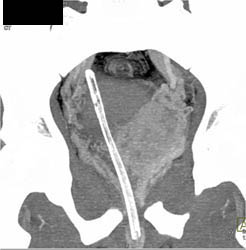

Diagnosis

Arrhythmias Causing Motion on Aortic Valve